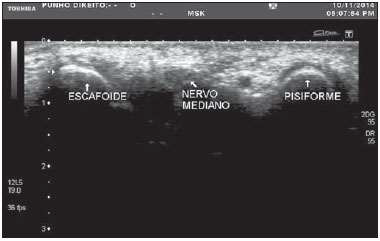

O.P.N, 60 anos, sexo feminino, costureira, obesa, hipertensa, diabética e moradora de Tracunhaém-PE, é encaminhada ao consultório de neurocirurgia com queixa de dor, dormência e formigamento em punho e dedos da mão direita que piora no fim do dia há 06 meses e com perda de força há 01 semana. É destra e relata episódios semelhantes nos últimos 06 meses, em especial quando precisa trabalhar muito. Trouxe resultado de ultrassonografia do punho direito com o diagnóstico de Síndrome do Túnel do Carpo (STC).